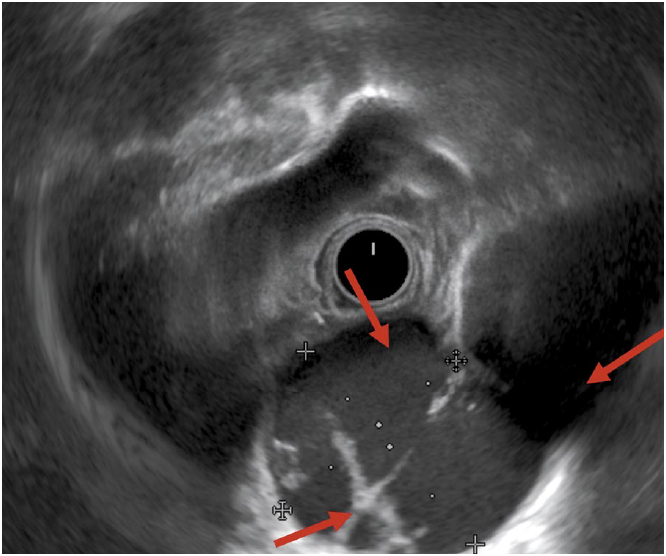

С целью верификации образования выполнена транспищеводная аспирационная биопсия. На уровне верхней трети пищевода лоцируется кистозное новообразование с наличием солидной части и перегородок. Новообразование прилежит к стенке пищевода, незначительно деформируя его просвет, и грудному отделу аорты (рис. 4).

Рис. 4. Эндосонографическая картина кистозно-солидного новообразования верхнего средостения.

Fig. 4. Endosonographic picture of the complex cystic-solid mass of the upper mediastinum.